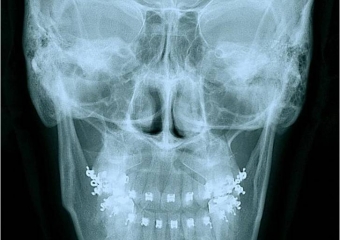

Telerradiografia frontal após a cirurgia - Clínica Cliniface

Telerradiografia frontal após a cirurgia